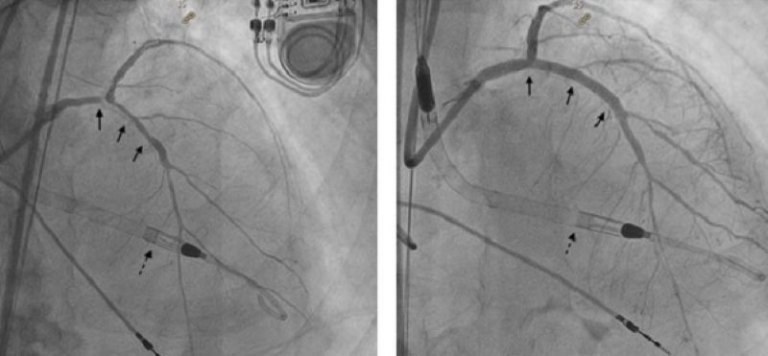

新竹臺大分院Impella微型心室輔助裝置協助高風險冠狀動脈介入治療 成功救治 88 歲心肌梗塞病人